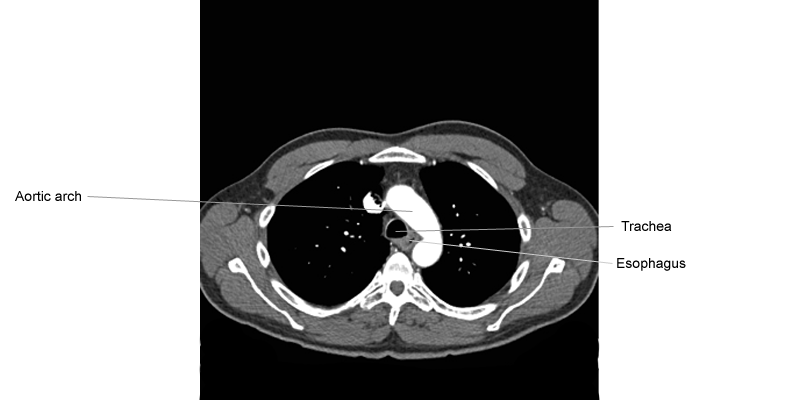

1. Axial Chest (Potongan Axial dari Thorax)